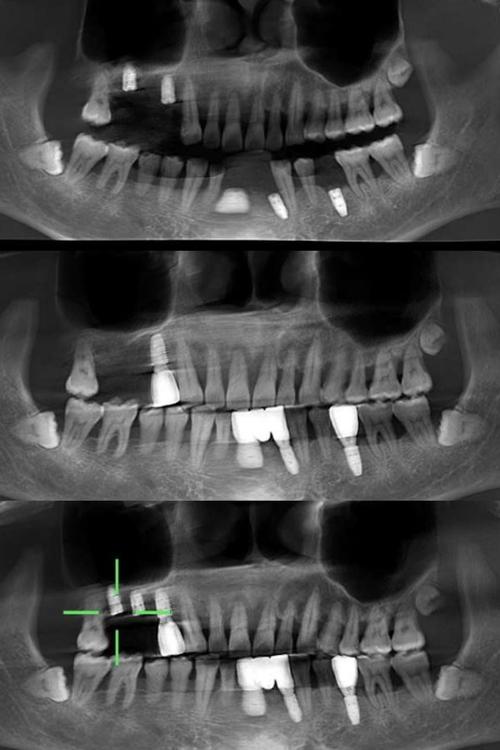

- 三维可视化:可任意角度旋转、切割图像,直观显示牙槽骨的立体形态,精确测量骨高度、宽度、厚度(误差可控制在0.1mm以内);

- 高分辨率:能清晰分辨下颌神经管、上颌窦底、颏孔等重要解剖结构的位置、边界及与牙槽嵴的距离;

- 规避神经血管损伤:对于下颌后牙区种植,CBCT可精确标记下颌神经管的走行,确保种植体尖端距离神经管至少1-2mm;

- 数字化种植导板设计:基于CBCT数据,结合口内扫描模型,可制作3D打印种植导板,引导种植体精准植入预定位置,误差小于0.5mm,尤其适合全口无牙颌种植或即刻种植病例。